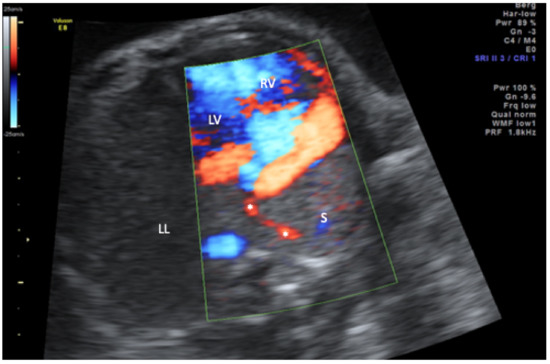

Scimitar syndrome is a rare disease characterized by hypoplasia of the right lung and partial anomalous pulmonary venous drainage to the inferior vena cava. All cases with a prenatal diagnosis of scimitar syndrome with or without associated malformations in an 18-year period (2000–2018) in two large tertiary referral centers (University of Bonn and University of Cologne, Germany) were retrospectively reviewed for the intrauterine course and postnatal outcome. Six cases were diagnosed in the study period. All presented with hypoplasia of the right lung, right-sided mediastinal shift, and abnormal pulmonary venous drainage to the inferior vena cava. Systemic arterial blood supply to the right lung, albeit postnatally present in all cases, could not be detected prenatally. Major associated anomalies were present in all cases and included atrial septal defect (n = 5), coarctation (n = 3), diaphragmatic hernia (n = 2), and VACTERL association (n = 1). Half of the cohort died within 6 months after birth and all three survivors suffer from long-term pulmonary sequelae. The primary hint to the prenatal diagnosis of scimitar syndrome is the abnormal position of the heart in the chest. If searched for, abnormal venous drainage can be identified prenatally and confirms the diagnosis. The prognosis depends on the presence of associated major anomalies and the need for neonatal intervention. Full article

Figure 1